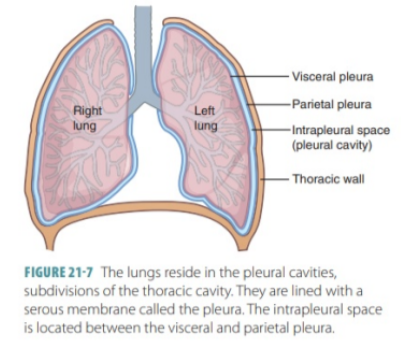

Pleural cavities

In the thorax we have 2 pleural cavities — each on either side of the mediastinum surrounding the lungs—

The medial wall of each pleural cavity is the mediastinum.

Each cavity is lined by a single layer of flat cells — the mesothelium — and an associated supporting connective tissue

Both layers form the actual “pleura”

Divided into 2 sections based on location —

Parietal pleura —

Outer section, associated with walls of the cavity

Visceral pleura —

Inner surface — adheres to and covers lungs

Pleural division based on location image

Parietal pleura —

Outer section, associated with walls of the cavity

Visceral pleura —

Inner surface — adheres to and covers lungs